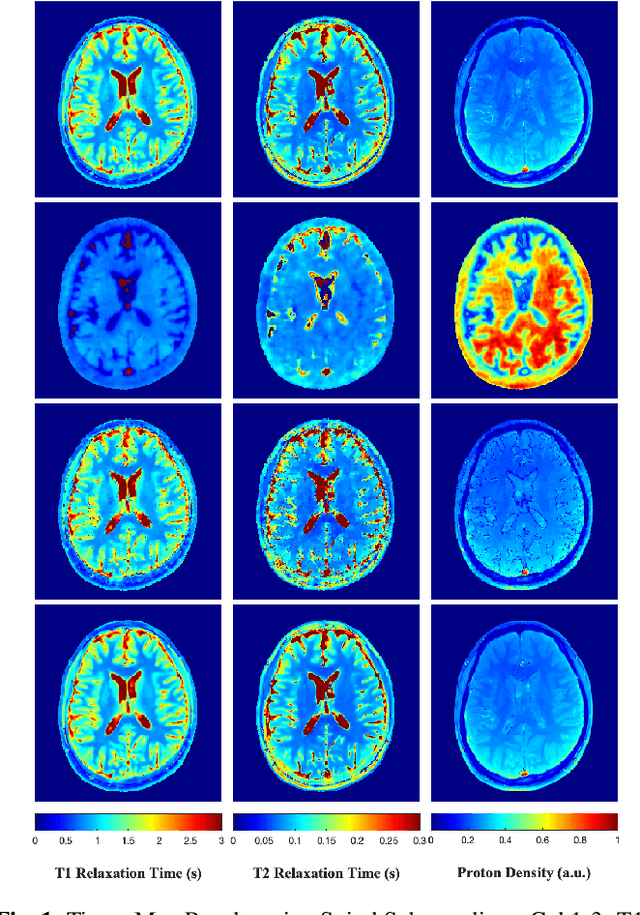

Abstract:Current state-of-the-art reconstruction for quantitative tissue maps from fast, compressive, Magnetic Resonance Fingerprinting (MRF), use supervised deep learning, with the drawback of requiring high-fidelity ground truth tissue map training data which is limited. This paper proposes NonLinear Equivariant Imaging (NLEI), a self-supervised learning approach to eliminate the need for ground truth for deep MRF image reconstruction. NLEI extends the recent Equivariant Imaging framework to nonlinear inverse problems such as MRF. Only fast, compressed-sampled MRF scans are used for training. NLEI learns tissue mapping using spatiotemporal priors: spatial priors are obtained from the invariance of MRF data to a group of geometric image transformations, while temporal priors are obtained from a nonlinear Bloch response model approximated by a pre-trained neural network. Tested retrospectively on two acquisition settings, we observe that NLEI (self-supervised learning) closely approaches the performance of supervised learning, despite not using ground truth during training.